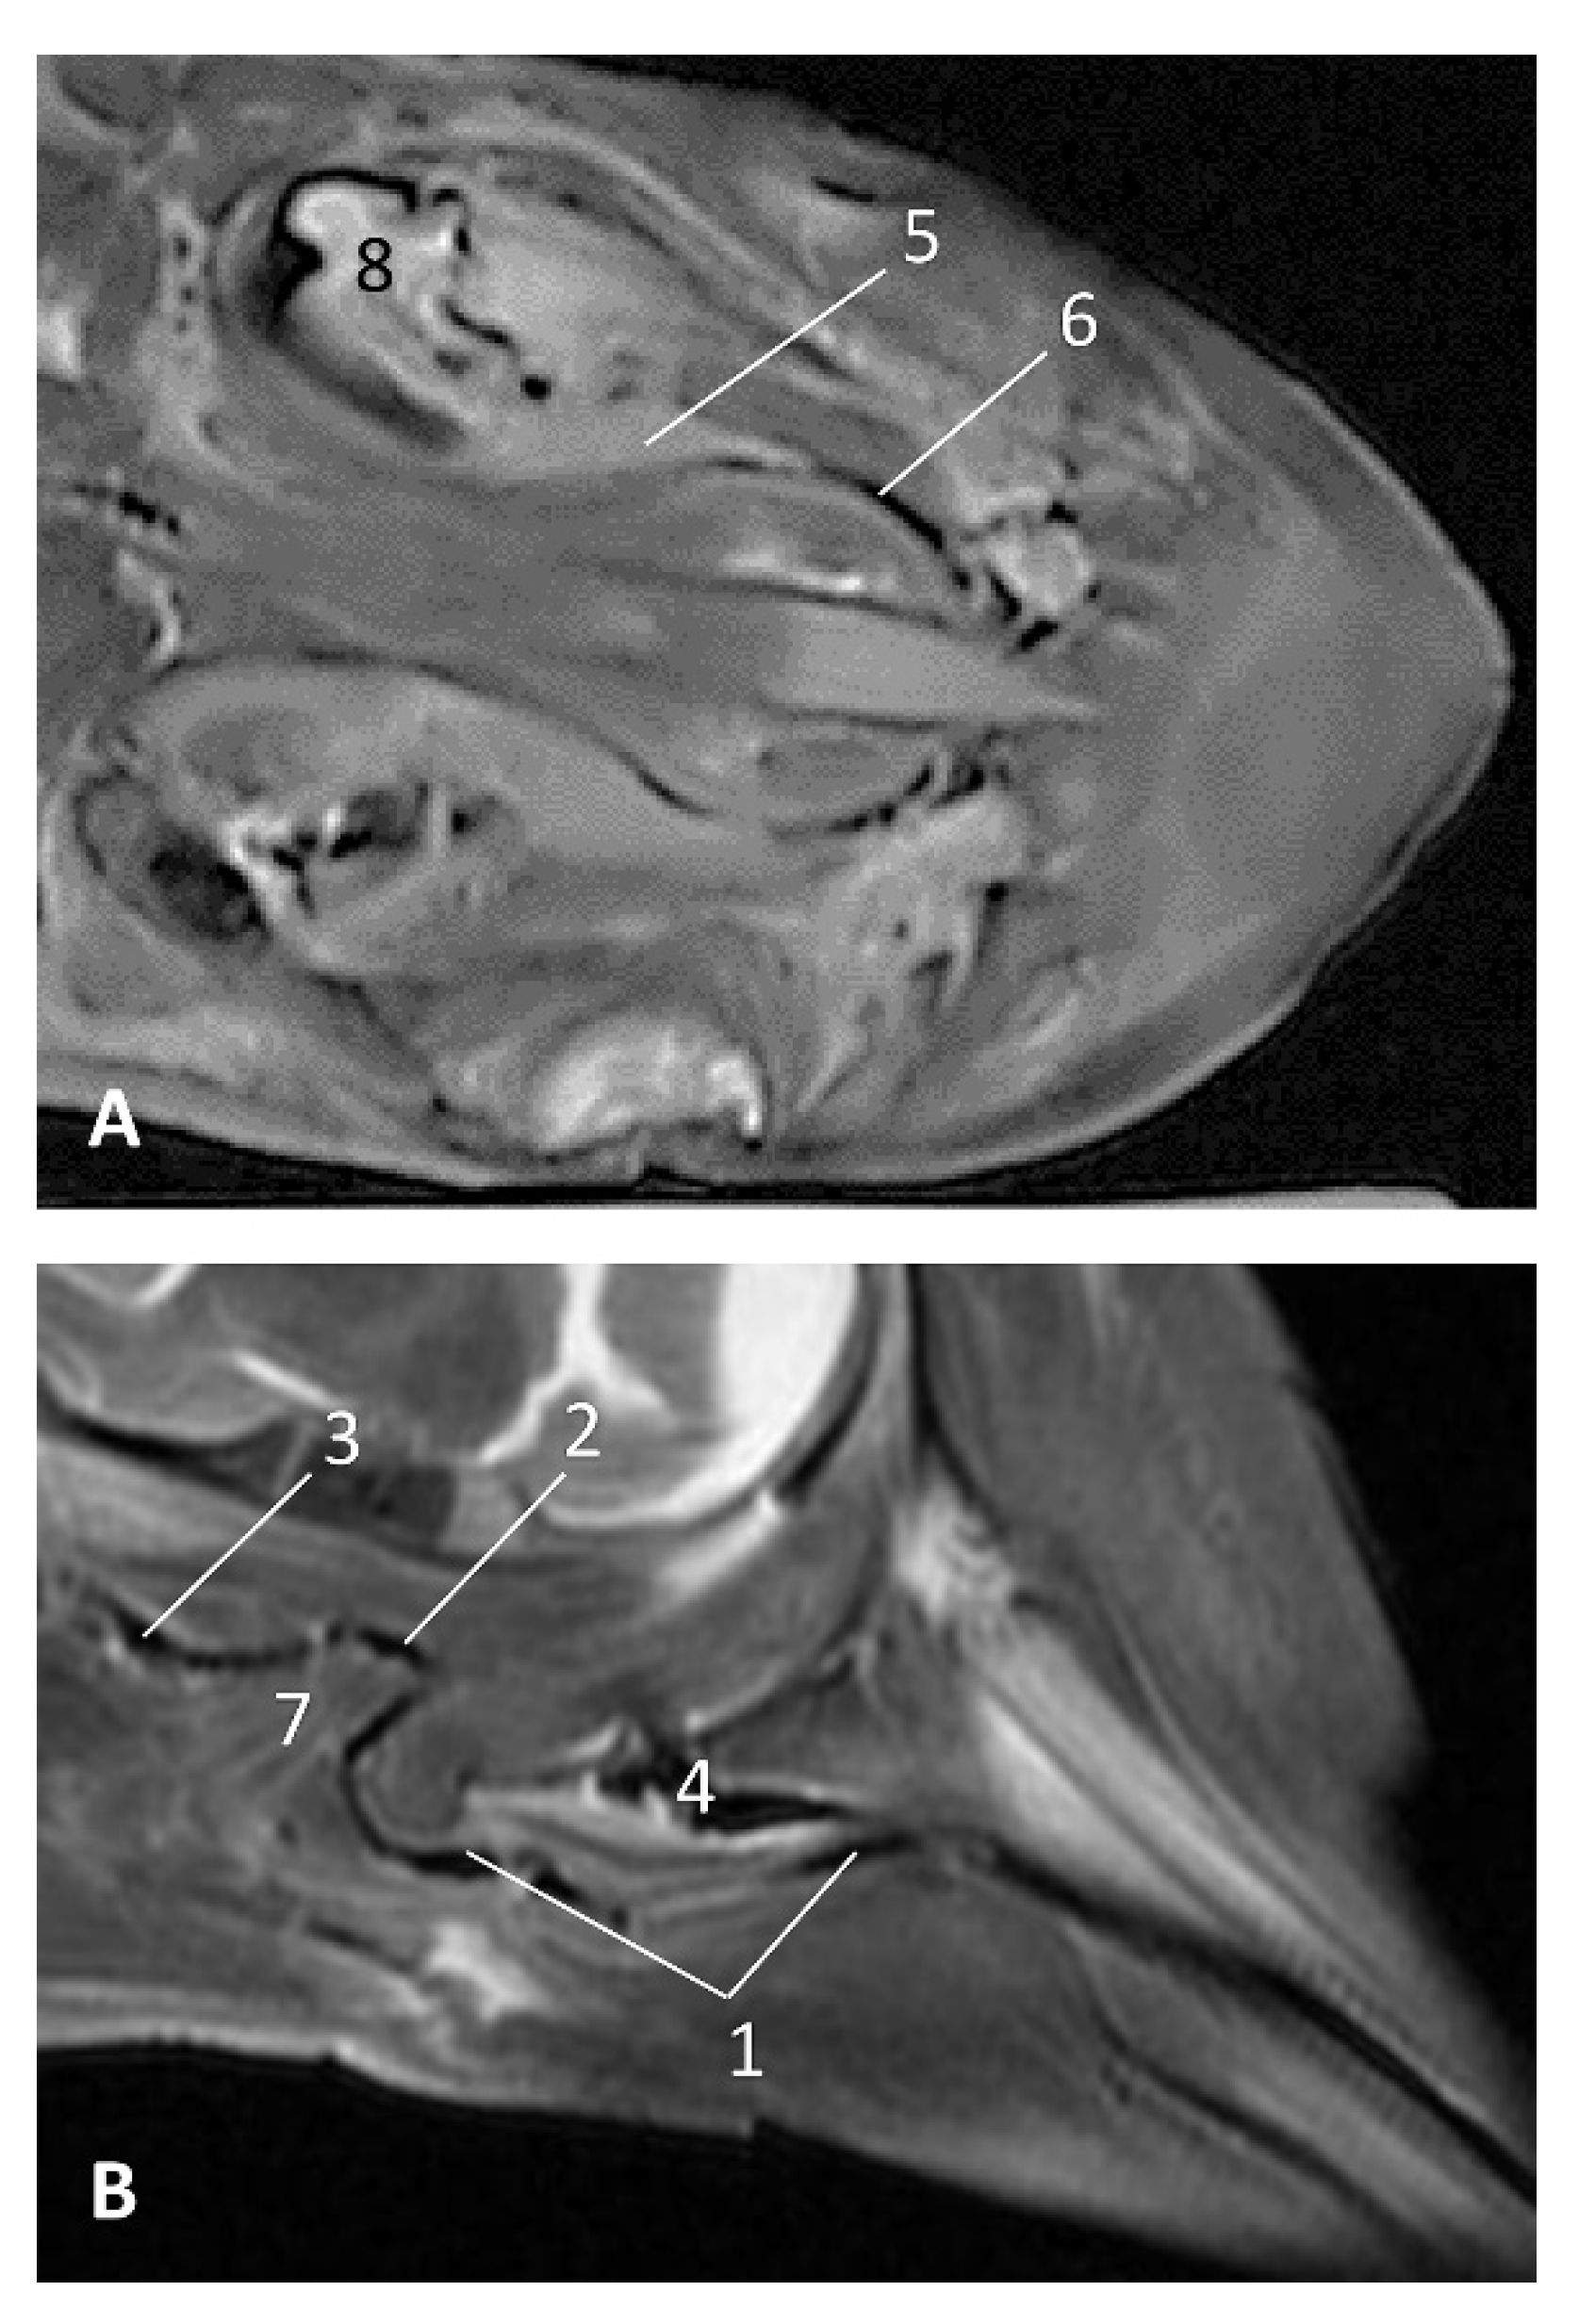

In older Delphinus delphis fetuses (dde5, dde8, dde11) this double space at both sides of the laryngopharynx is more evident and shows the same intensity, but now we can distinguish the vascular area (hyperintense) and the air-filled area (hypointense) (Figure 27, Figure 28, Figure 29, Figure 30 and Figure 31).

Figure 27.

Images of the pharyngeal cavity. MR coronal and sagittal images are oriented so that the rostral is to the right. (A,B) T2 FrFSE sagittal, (C) T1 SE and (D) T2 FrFSE coronal planes. 5.5 months, dde5. 1, Inner ear; 2, Pharyngeal diverticulum of the auditory tube: moderate hyperintense area (vascular); 3, Pharyngeal diverticulum of the auditory tube: hypointense area (air).

Figure 28.

Images of the pharyngeal cavity. MR sagittal and coronal images are oriented so that the rostral is to the right. (A) T1 SE sagittal, (B) T2 FrFSE sagittal, (C) T1 SE coronal and (D) T2 FrFSE coronal planes. 6 months, dde8. 1, Inner ear; 2, Pharyngeal diverticulum of the auditory tube: moderate hyperintense area (vascular); 3, Pharyngeal diverticulum of the auditory tube: moderate hypointense area; 4, Pharyngeal diverticulum of the auditory tube: hypointense area (air); 5, Pharyngeal diverticulum of the auditory tube: hyperintense area (vascular).

Figure 29.

Images of the pharyngeal cavity. (A,B) MR coronal and sagittal images are oriented so that the rostral is to the right. (A,B) T2 FrFSE coronal and sagittal planes. 8 months, dde11. 1, Oropharynx: fauces; 2, Nasopharynx; 3, Laringopharynx: oesophageal vestibule; 4, Nasopharynx: pharyngeal diverticulum of the auditory tube; 5, Pharyngeal diverticulum of the auditory tube: hyperintense area (vascular); 6, Pharyngeal diverticulum of the auditory tube: hypointense area (air); 7, Larynx; 8, Middle and inner ear.

Figure 30.

Images of the pharyngeal cavity. MR sagittal and coronal images are oriented so that the rostral is to the right. (A) T1 SE sagittal, (B) T2 FrFSE sagittal, (C,E) T1 SE coronal and (D,F) T2 FrFSE coronal planes. 4 months, dde14. 1, Inner and middle ear; 2, Pharyngeal diverticulum of the auditory tube (vascular); 3, Pharyngeal diverticulum of the auditory tube (air); 4, Auditory tube; 5, Nasopharinx; 6, Intrapharyngeal orifice.

Figure 31.

Images of the pharyngeal cavity. MR sagittal and coronal images are oriented so that the rostral is to the right. (A) T1 SE sagittal, (B) T2 FrFSE sagittal, (C) T1 SE coronal and (D) T2 FrFSE coronal planes. 9 months, grgr1. 1, Inner and middle ear; 2, Pharyngeal diverticulum of the auditory tube: vascular; 3, Pharyngeal diverticulum of the auditory tube: air; 4, Mandibles.

In more advanced fetal development, it is possible to observe air (hypointense) and vascular (moderate hyperintense) areas, and even the auditory tube (slightly hypointense) (Figure 30).

PDAT were clearly seen in sagittal and coronal sections in a Grampus griseus fetus (grgr1). The T2 sequences are clearer than T1 because they differentiate two areas: slightly hypointense (vascular) and hyperintense (air) (Figure 31).